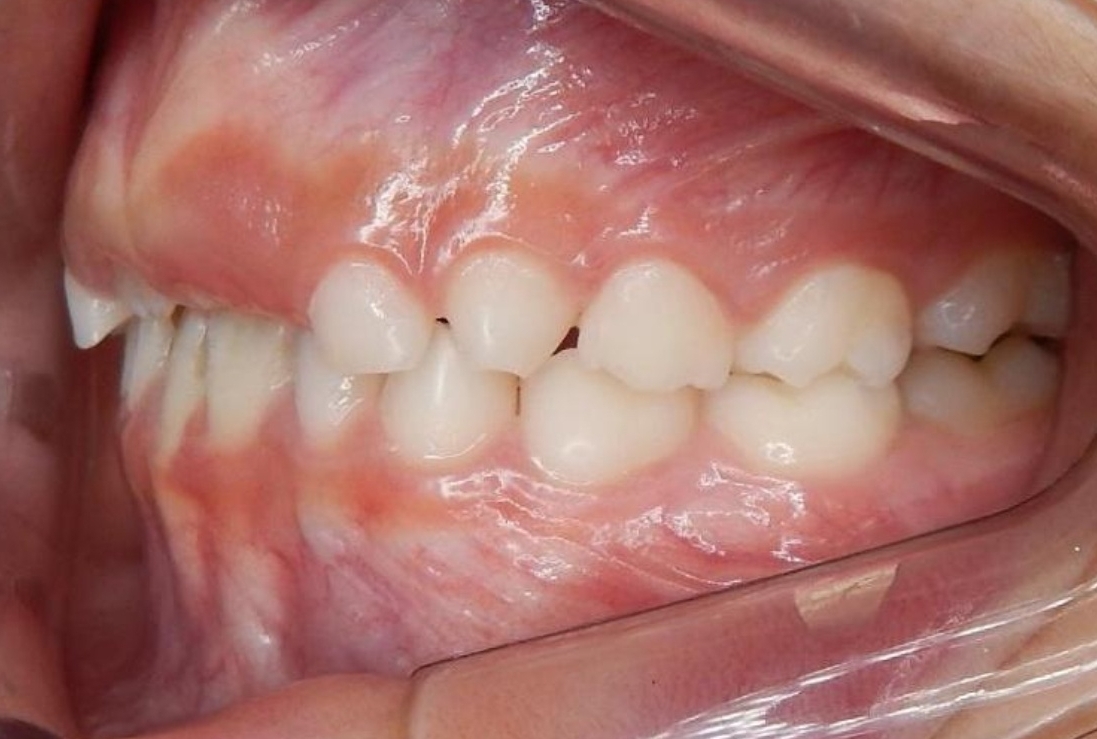

ORTODONTIA MIOFUNCIONAL

J.N.E.